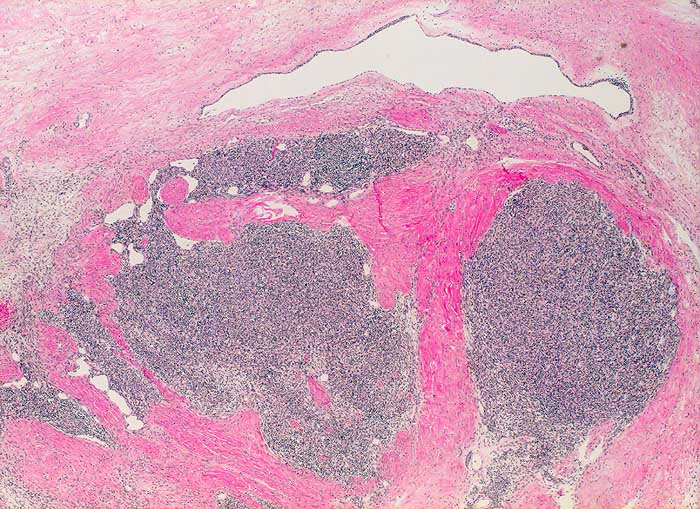

PathoPic – image database / PathoPic ID 5973 - Thymom Typ A (WHO)

Thymom Typ A (WHO)

Lobulierter bekapselter Tumor. Fokale Zystenbildung.

Es handelt sich hier um ein grosses gutartiges Thymom ohne maligne Zellelemente. Der Tumor in überwiegenden Anteilen mit einem medullären Phänotyp mit spindeligen Tumorzellen, entsprechend einem medullären Thymom nach der Müller-Hermelink-Klassifikation und einem Typ A-Thymom nach der WHO-Klassifikation. Der Tumor allseits umkapselt und im Gesunden entfernt ohne invasives Wachstum. Insgesamt hat das Thymom vom Typ A bei vollständiger Umkapselung und Entfernung im Gesunden eine sehr gute Langzeitprognose.

Histologie

25